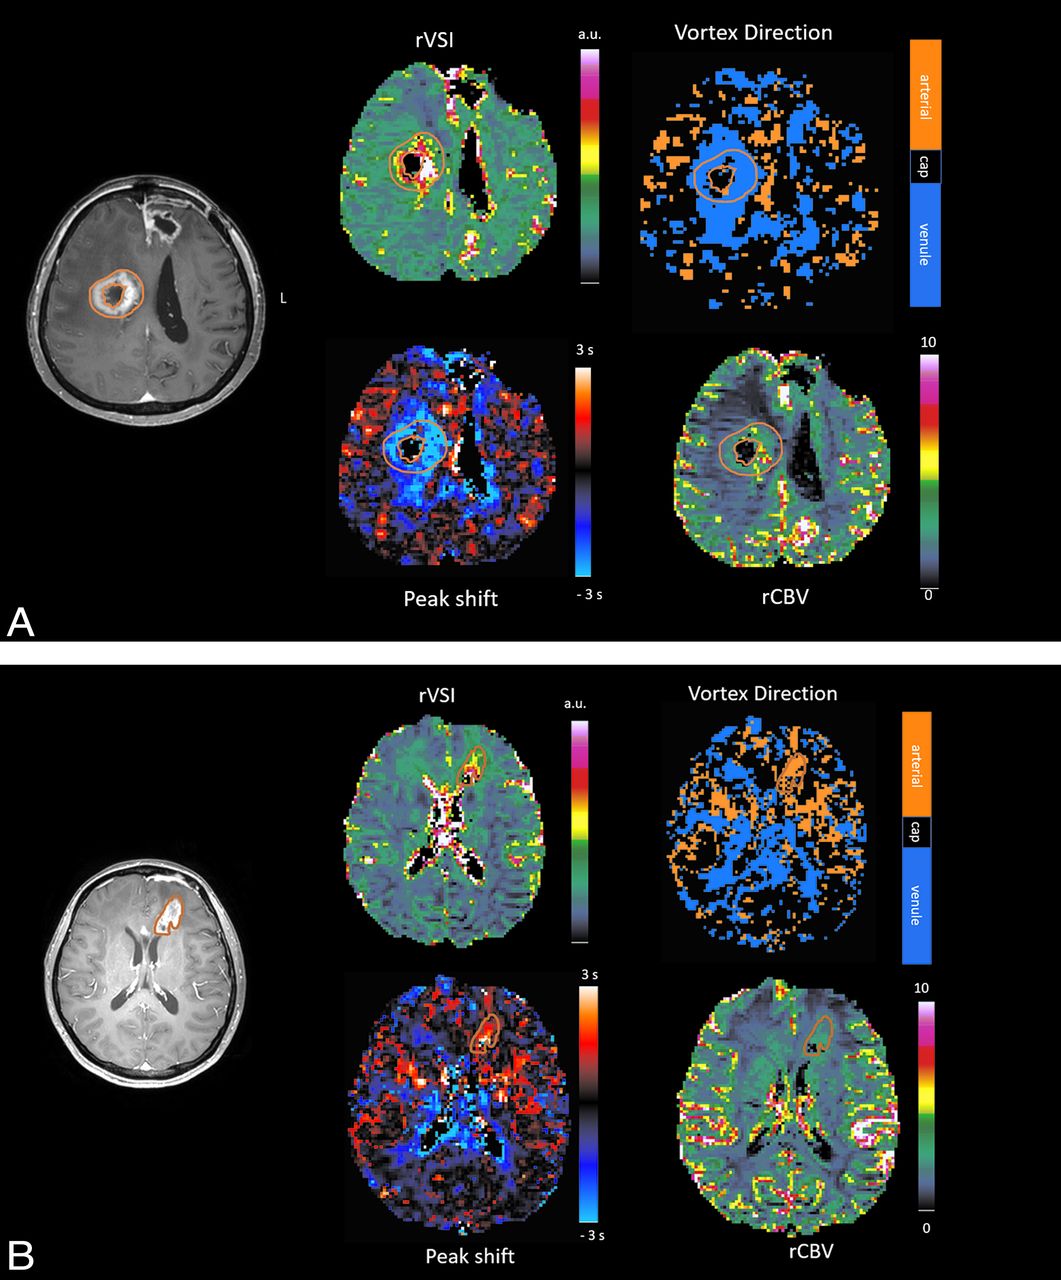

DSC and VAI parameters are summarized in Table 2. Patients with PP showed significantly lower rCBV (mean PP = 1.38 [SD, 0.53] versus mean ETP = 1.88 [SD, 0.78], P = .02) and a tendency toward a smaller rVSI (PP = 83.17 [SD, 40.60] versus ETP = 99.67 [SD, 38.78], P = .15) compared with patients with ETP. Patients with PP showed a significantly higher positive peak shift compared with those with ETP (PP = 0.33 [SD, 0.77] versus ETP = −0.02 [SD, 0.36], P = .02). The arterial dominance score was significantly higher in the PP group compared with the ETP group (PP = 2.11 [SD, 0.6] versus ETP = 1.46 [SD, 0.7], P = .001). Figure 3 shows representative cases of PP and ETP, and corresponding signal intensity curves with hysteresis plots are provided in the Online Supplemental Data.

A, Early tumor progression. A 53-year-old woman who completed concurrent chemoradiotherapy 8 weeks ago developed a necrotic enhancing mass in the right frontal lobe surrounding the surgical cavity. On the rCBV map and rVSI map, rCBV is increased with a high rVSI in the corresponding area. A negative peak shift on the peak shift map with venous dominance on the vortex direction map is noted, and an arterial dominance score of 1 was assigned. B, Pseudoprogression. A 67-year-old woman who completed CCRT 10 weeks ago developed a necrotic enhancing mass in the left frontal lobe. On the rCBV and rVSI maps, rCBV is mildly increased with a lower rVSI than in the patient with ETP. A positive peak shift on the peak shift map and arterial dominance on the vortex direction map are shown, and an arterial dominance score of 3 was assigned.